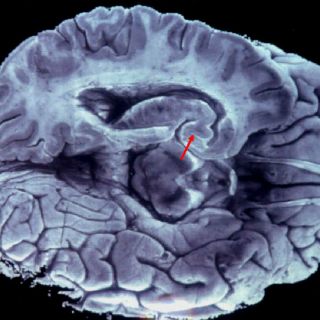

La amígdala es una de las partes más profundas del cerebro, que, desde el punto de vista evolutivo cuenta con estructuras subcorticales antiguas, como, además de la amígdala, el hipocampo, y otras posteriores como la corteza, la parte externa que cubre los dos hemisferios.

Esta parte del cerebro es la encargada de procesar el miedo y la mayor parte de las emociones de carga negativa como la ira.

Sin embargo, dado que la amígdala es una estructura muy profunda del cerebro, estas técnicas carecen de la resolución suficiente para ver cómo funciona el proceso. Hacen falta otras técnicas, como el uso de electrodos implantados en esta región cerebral.